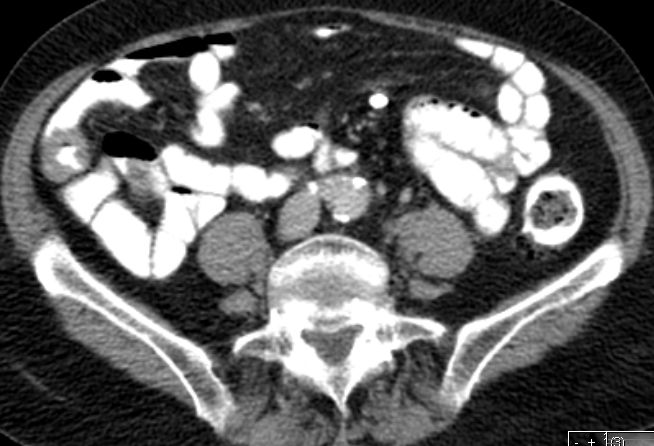

Oft im Gesicht (v.a. Kiefer) oder am Hals. | Innere Organe (v.a. im Bauchraum), im Spätstadium auch ZNS, Knochenmark, Meningen. | ||

Burkitt-Lymphom täuscht einen Dünndarmtumor vor.

Exzision anlässlich einer Rektum-Ca-OP bei einer 80jährigen Frau. | ||||